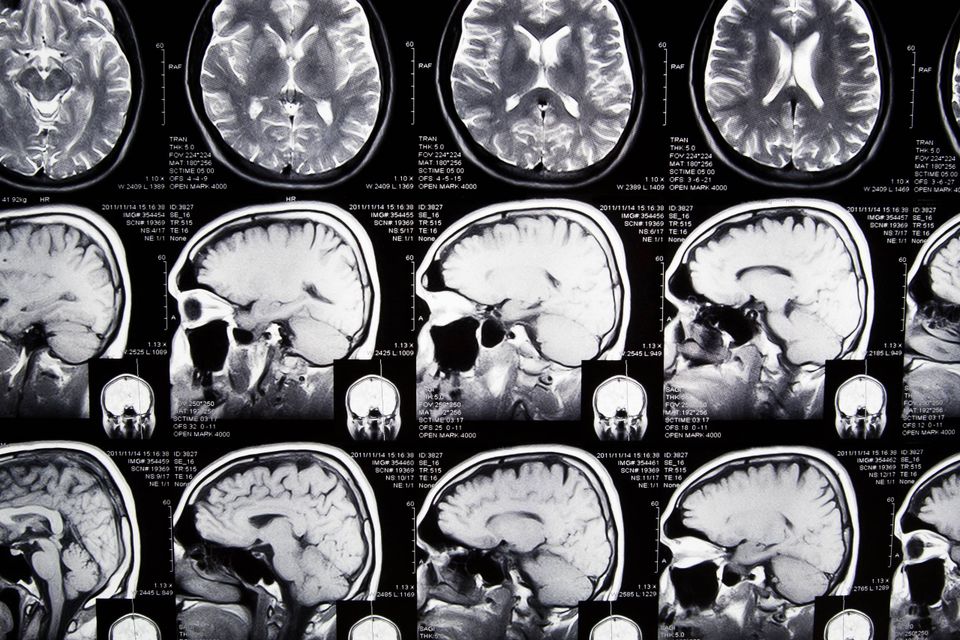

Michael A. Freeman forsker i iværksætteres mentale billede.